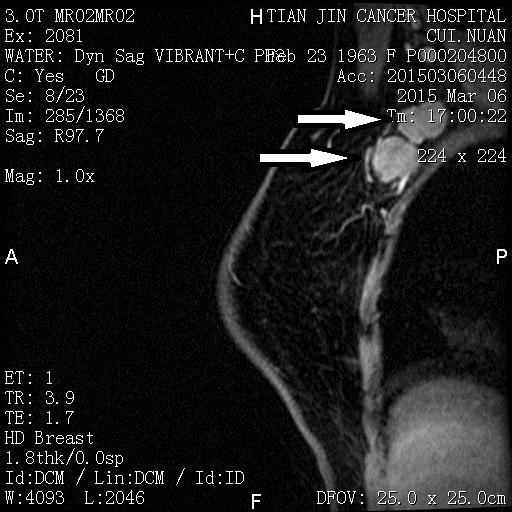

新辅助化疗后MRI

*箭头处原发病灶消失

*箭头所指为内乳区淋巴结残留影像

*箭头所指为腋窝淋巴结残留影像